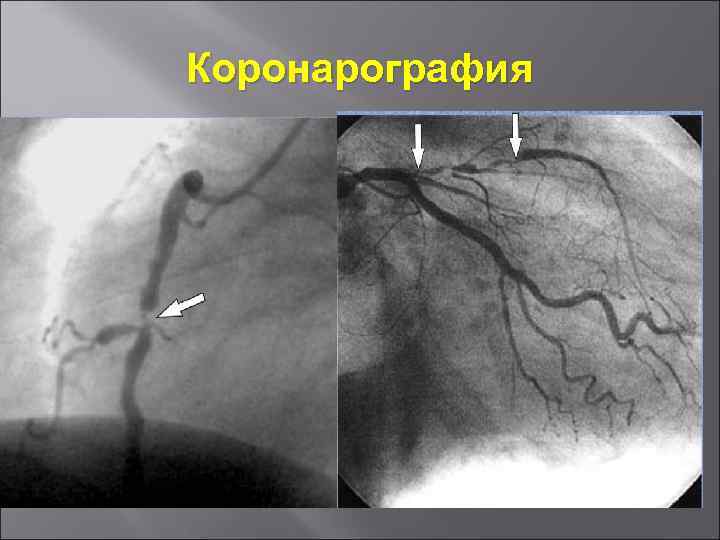

Коронарография

Коронарография